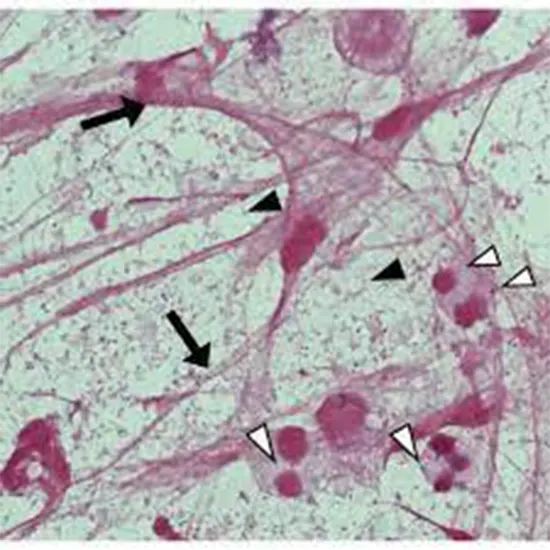

A laboratory test called Gram Stain is in sputum samples. Sputum is the substance that emerges from a patient's airway after a vigorous cough. The bacterial illness may impact your lower respiratory tractChildren under the age of five, patients over the age of 65, and those with weakened immune systems are typically affected by the virus. After its creator, Hans Gram, the test was gramedram Stain sputum. Your respiratory system produces sputum, which is a saliva and mucus mixture.